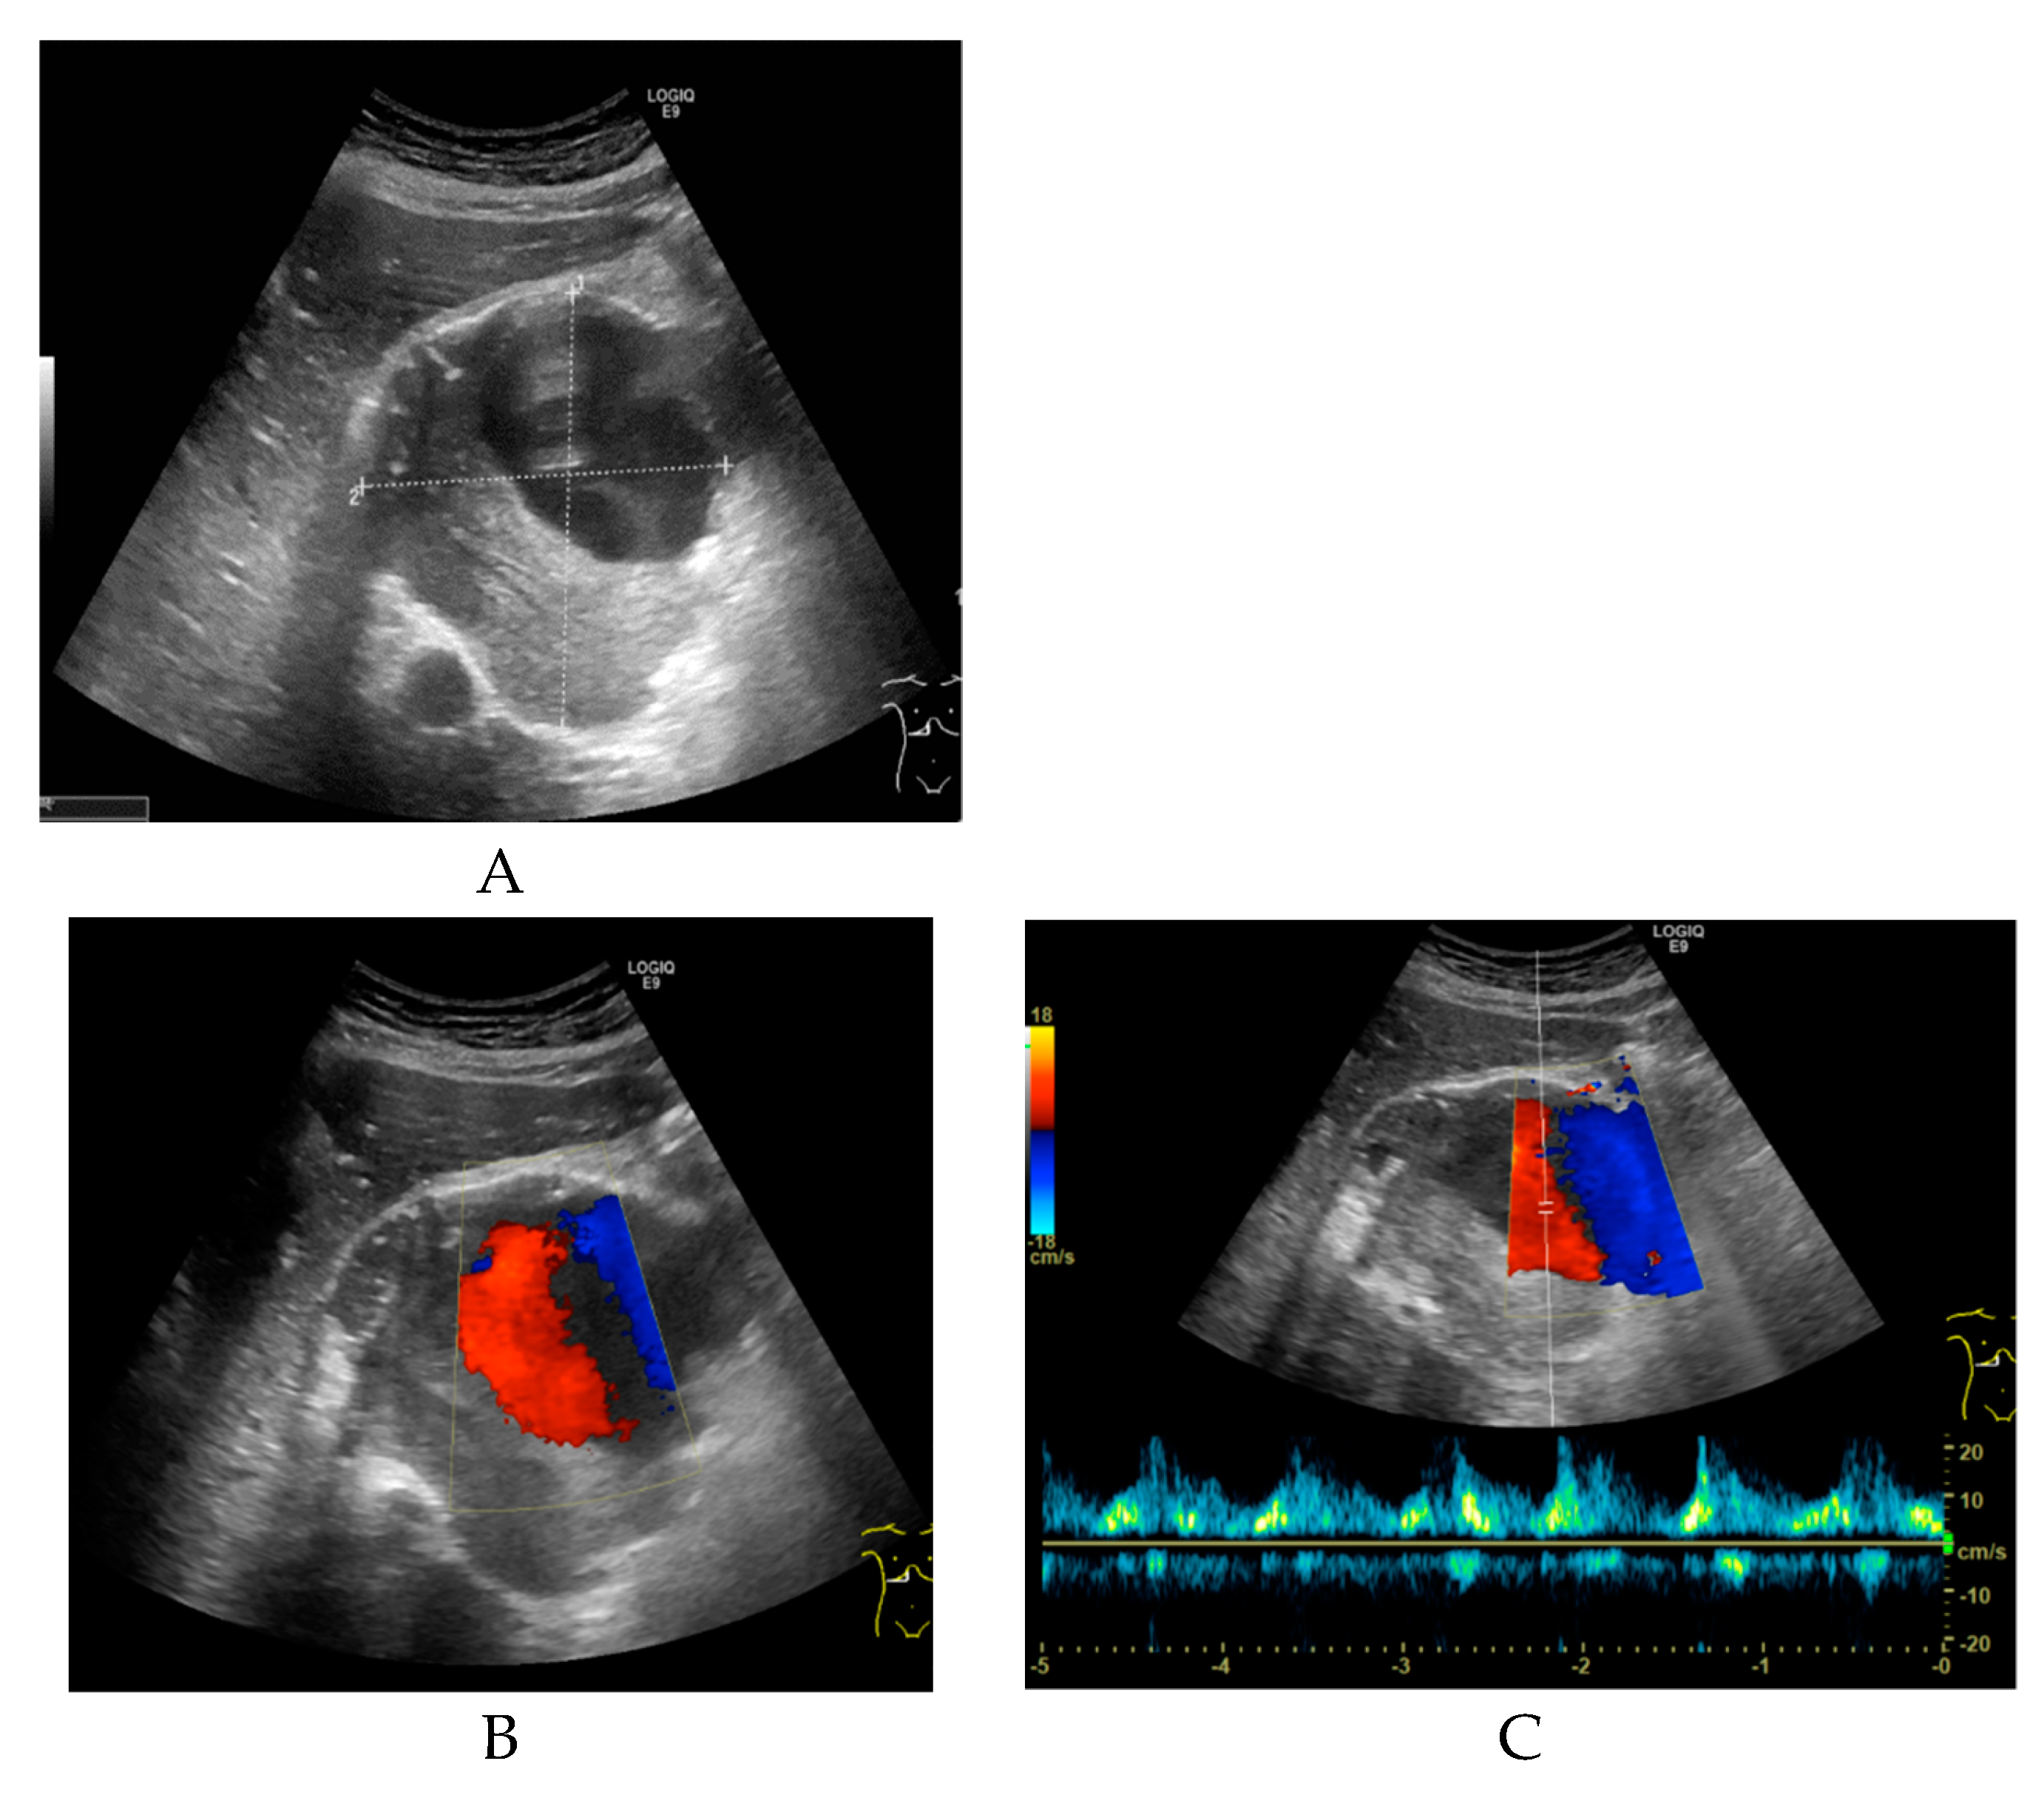

2. Case Report